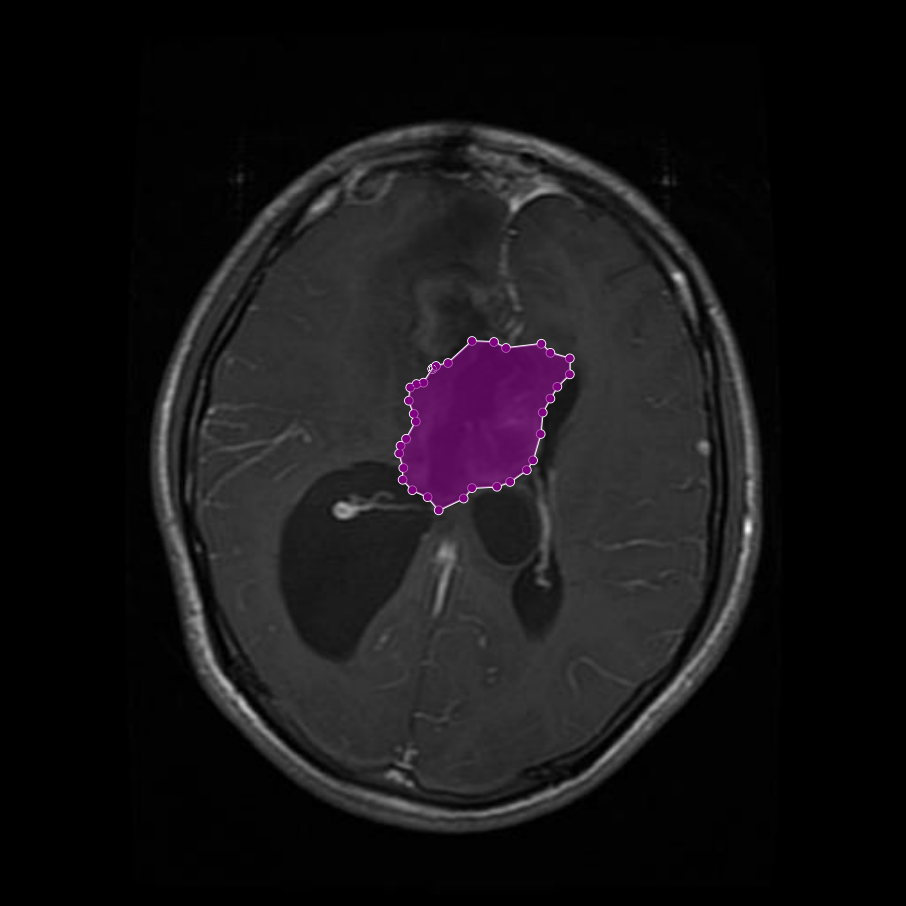

Figure 1: Samples of Glioma segmentation across different imaging planes

Glioma: Gliomas are irregularly shaped and often infiltrate surrounding tissues, presenting significant challenges for precise boundary definition. These complexities require robust segmentation techniques to capture their variable morphology. As shown in Figure 1, gliomas exhibit irregular and diffuse growth patterns, which are highlighted through annotated tumor masks.